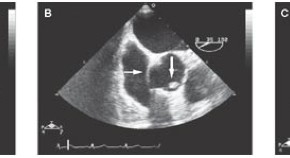

• Lindsay et al. present an interesting case of a patient with a ruptured sinus of Valsalva aneurysm. The authors recommend the early use of imaging modalities for prompt diagnosis, as anticoagulation therapy might have detrimental effects on patient outcome. Reparative surgery is safe and successful in almost all noninfective cases.